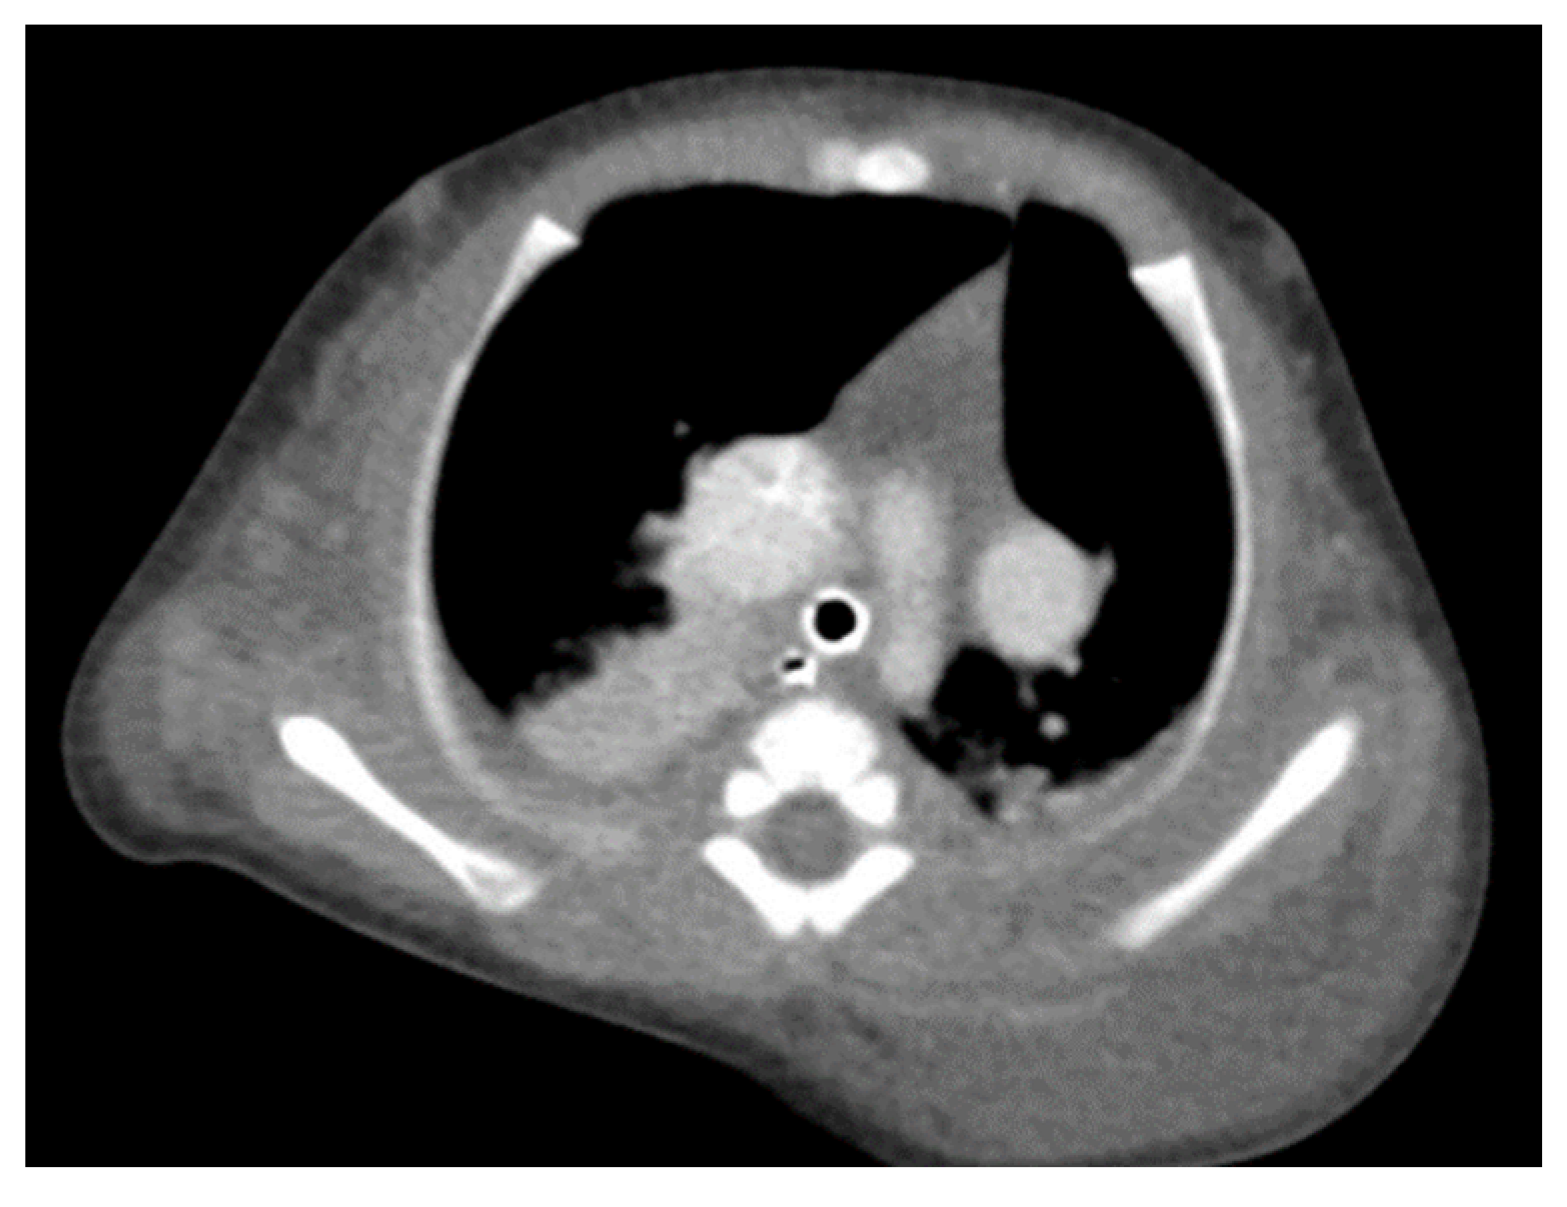

Through thoracic CT, we found SVC with a diameter of 15 mm (Figure 1), a venous collector with a 12 mm in diameter connected to the SVC and identified at the level of a plane passing through the middle of the left superior pulmonary lobe (Figure 2). The venous structure continues superiorly with the left brachiocephalic venous trunk, which was dilated up to 12 mm (Figure 3) and inferiorly with a left pulmonary vein. The pulmonary trunk appeared shorter, with a diameter of 6 mm, right pulmonary artery = 5.4 mm and left pulmonary artery = 5.6 mm (Figure 4 and Figure 5). We have identified traits of pulmonary consolidation (Figure 6).

Figure 2.

Venous collector.